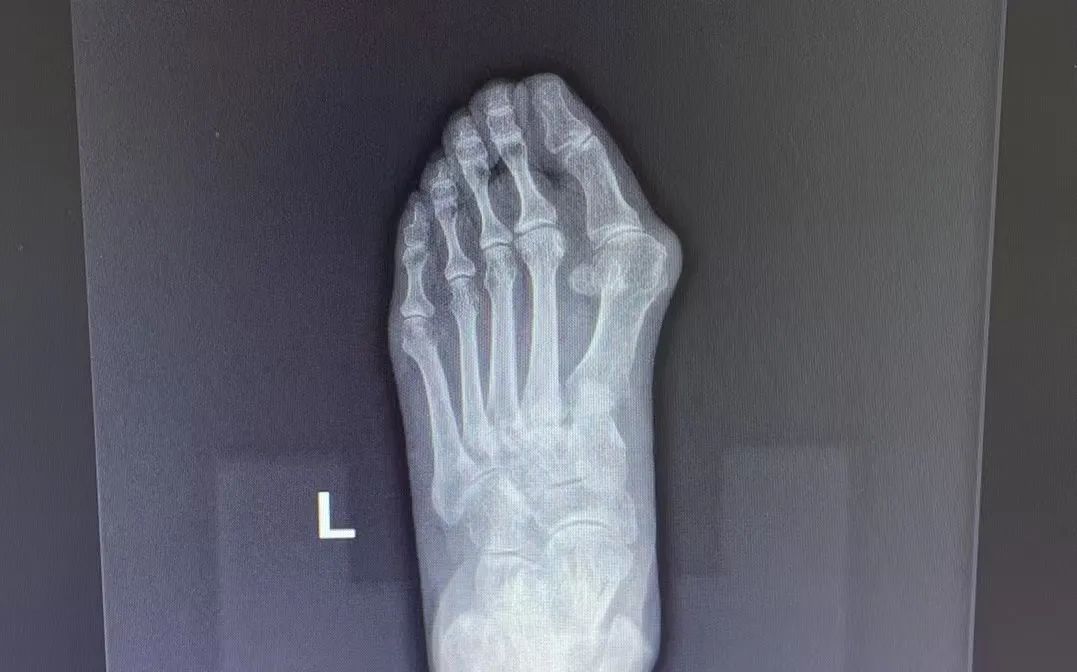

△患者手術(shù)前后比對(duì)

對(duì)于非手術(shù)干預(yù)無(wú)效或嚴(yán)重影響生活質(zhì)量的患者,可考慮手術(shù)干預(yù)。